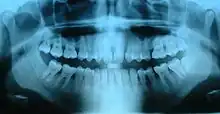

Ortopantomografía

La ortopantomografía o radiografía panorámica es una técnica radiológica que representa, en una única película, una imagen general de los maxilares, la mandíbula y los dientes. Por tanto, es de primordial utilidad en el área dentomaxilomandibular.

Su papel en el diagnóstico odontológico, no solo de los dientes sino también del maxilar y mandíbula, es fundamental. Sin la ortopantomografía, el odontólogo perdería una gran ayuda en la mayoría de las especialidades de su campo. Prácticamente, es utilizada de forma sistemática en odontología, llegando a ser un arma diagnóstica rutinaria. El valor diagnóstico de la ortopantomografía en cirugía bucal, implantología, ortodoncia, periodoncia y en patología oral y dental está claramente demostrado.

El término de radiografía panorámica es el más comúnmente utilizado, ya que la radiografía resultante muestra una visión panorámica de la cara y parte inferior de la cabeza. Laudenback describe la ortopantomografía como uno de los inventos radiológicos más originales de los últimos decenios. El 40 % de los hallazgos patológicos principales y secundarios se descubren a partir de ella. Amplía el campo de diagnóstico en un 70 % y reduce la dosis de radiación de la superficie cutánea en un 90 % con respecto a las series radiográficas periapicales.